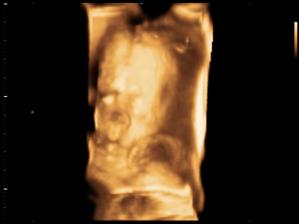

Zda sa ze nase 1. a snad aj posledne ICSI s PK sa podarilo🙂

Onedlho nás uvidíte ako malé bodky na sone,